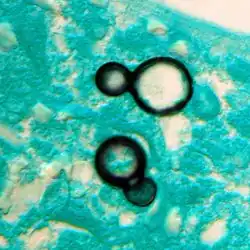

Blastomyces dermatitidis, el agente causal de la blastomicosis. | ||

La forma infectante son las conidiosporas ovales o piriformes, de 2 a 7 μm de pared delgada y lisa, que se forman sésiles o pediculadas sobre las hifas de la fase miceliana, algodonosa y blanquecina aunque se oscurece con la edad. Por cultivo en Agar BHI con cisteína y 5% de sangre, a 37 °C, se produce el cambio a la fase levaduriforme patógena, con blastosporas multinucleadas de pared gruesa, gemación generalmente simple de base amplia y 8-15 μm, en colonias morenas, arrugadas y butirosas. El cultivo de conidiosporas o de blastosporas a 24 °C en Agar Sabouraud Glucosado (SDA), da las colonias blanquecinas, algodonosas y circunscritas propias de la forma miceliana.

La lesión elemental es un granuloma de centro necrótico, rico en blastosporas, envuelto en una capa de células epitelioides, y periferia con abundantes linfocitos, algunos macrófagos y células gigantes de cuerpo extraño, y poca tendencia a la encapsulación o a la caseificación. En las lesiones supurantes predominan polimorfonucleares y macrófagos.

- Micológico: las abundantes blastosporas redondeadas de gran tamaño y gruesa pared en los tejidos carecen de cápsula hialina, pero podrían confundirse con criptococos. Se ven muy bien en azul de metileno o Giemsa.

- El cultivo a 37 °C en Agar BHI-cisteína-Sangre muestra el típico crecimiento levaduriforme, con grandes blastosporas multinucleadas acapsuladas de gruesa pared y gemación de base amplia, que al resembrar en SDA a 25-30 °C forma el micelio algodonoso con conidióforos simples y pequeñas conidias, propio de Blastomyces.